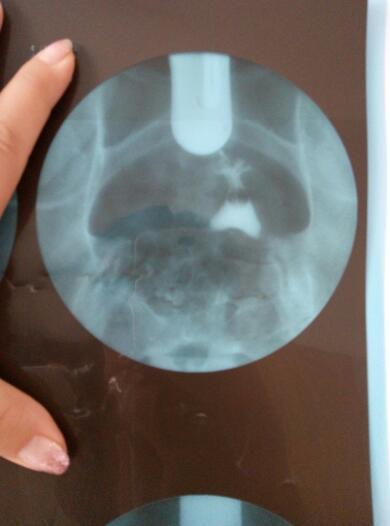

帮我看看,什么情况,还能自然受孕吗?不做手术吃药能解决吗?好人一生平安 点击展开 匿名用户 2016-06-01 09:40 满意回答 根据你的输卵管造影检丛遮查结果显示,筝扬露应该考虑是属于输卵管阻塞等原因引起的症且脑状,应该是比较难自然受孕的,应该积极进行治疗。可以考虑进行输卵管通水治疗的。必要时可以考虑进行宫腔镜,三镜一丝等手术治疗。 太阳荣华医师 2016-06-01 10:03 宝宝知道提示您:回答为网友贡献,仅供参考。 相关问题 请问这是什么?好人一生平安帮我看看吧 朋友们懂得人帮我看看,像这样的报告我想做人工受孕的机率大吗? 一个朋友结婚四年多了,他老婆不孕 现在医院要她做手术治疗 先吃了催排药打算现让他们试一个月自然受孕